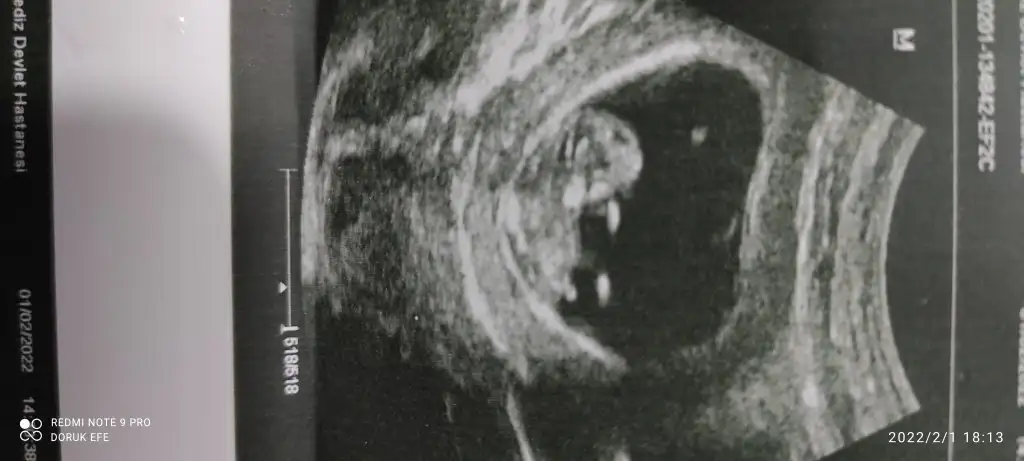

dr soylemeden siz gorun genital nub teorisi ( bebegin cinsiyeti)

Ikra meyra Ikra meyra merhabalar bakabilir misiniz 💛

Renkli den de bakıyomusunuz acaba cinsiyete ? Ikra meyra Ikra meyra